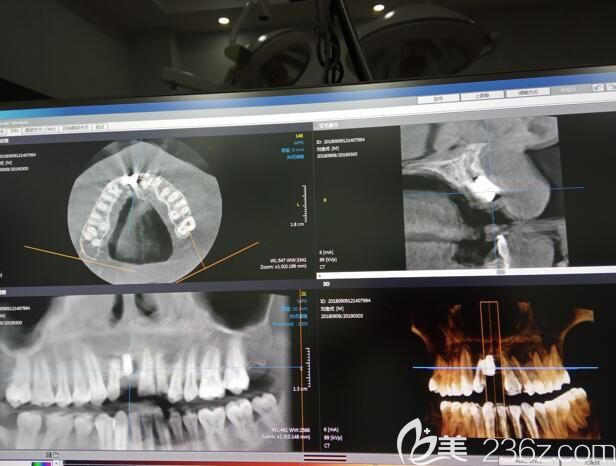

岑志平醫(yī)生和我溝通后,做了CT檢查、拍片對(duì)牙槽骨量進(jìn)行測(cè)量和評(píng)估,又用全數(shù)字化電腦設(shè)計(jì)了種植方案,并且可以先看了種植牙后的效果,然后我選擇了性價(jià)比較高的韓國登騰種植體。